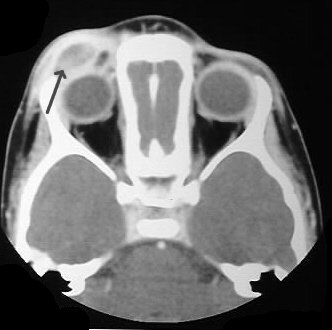

- En cráneo: Lesión lítica redonda/u oval, bordes bien definidos ("en sacabocados"), a veces con fragmento óseo central (botón secuestro).

Tomografía Computarizada (TC) y Resonancia Magnética (RM)

TC: Mejor para definir destrucción ósea y reacción perióstica. RM: Estudio de elección para evaluar extensión y diagnóstico diferencial.